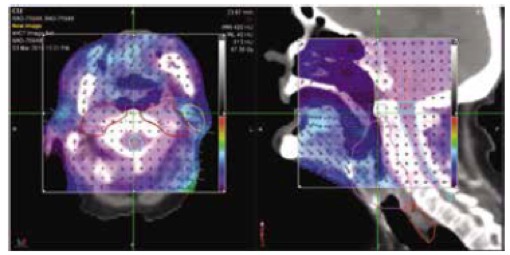

I. Delivery Analysis

Το σύστημα Delivery Analysis επεξεργάζεται με τρόπο αυτόματο τα δεδομένα από την εκτέλεση της θεραπείας κάθε ασθενούς και ελέγχει αν κάθε συνεδρία αποδίδεται όπως έχει σχεδιαστεί.

- Για κάθε ασθενή, το Delivery Analysis ελέγχει τη σωστή λειτουργία του κατεθυντήρα πολλαπλών φύλλων χρησιμοποιώντας το σήμα του ενσωματωμένου ανιχνευτή του συστήματος TomoTherapy. Σε περίπτωση εμφάνισης διαφορών το σύστημα αυτόματα υπολογίζει την επίδραση τους στην κατανομή της χορηγούμενη δόσης και ειδοποιεί τον ακτινοφυσικό και τον ιατρό.

- Σε κάθε συνεδρία το σύστημα μετράει και επεξεργάζεται την ροή φωτονίων στην έξοδο του ασθενούς (exit fluence) για να εξασφαλίσει την σωστή εκτέλεση της θεραπείας από την πρώτη έως την τελευταία συνεδρία.

Εύχρηστο περιβάλλον εργασίας

- Το σύστημα Delivery Analysis αναλύει τα δεδομένα από την εκτέλεση της θεραπείας και τα παρουσιάζει με τρόπο άμεσο και ευανάγνωστο στους ακτινοφυσικούς και του ιατρούς του τμήματος. Το σύστημα ενσωματώνει εργαλεία για την λεπτομερή εξέταση όλων των επιμέρους στοιχείων της θεραπείας συμπεριλαμβανομένων της ακρίβειας τοποθέτησης του ασθενούς, την επίδοσης του συστήματος TomoTherapy κτλ.

Δοσιμετρικός έλεγχος πριν την εκτέλεση της θεραπείας

Το σύστημα Delivery Analysis παρέχει τα απαραίτητα εργαλεία για τον ποιοτικό έλεγχο των πλάνων θεραπείας κάθε ασθενούς. Συγκεκριμένα:

- πριν την έναρξη της θεραπείας εκτελείται μια διαδικασία δοσιμετρικού ποιοτικού ελέγχου,

- το σύστημα Delivery Analysis συλλέγει τα δεδομένα από τον ενσωματωμένο ανιχνευτή του συστήματος και

- ανακατασκευάζει την μετρούμενη κατανομή δόσης στις εικόνες αξονικής τομογραφίας του ασθενή και την συγκρίνει με αυτή του πλάνου θεραπείας

Ποιοτικός έλεγχος της ακρίβειας χορήγησης της θεραπείας

- Κατά την διάρκεια εκτέλεσης κάθε συνεδρίας και για κάθε ασθενή το σύστημα Delivery Analysis μετράει αυτόματα με τον ενσωματωμένο ανιχνευτή την ροή των φωτονίων στην έξοδο του ασθενούς

- Το σύστημα Delivery Analysis αναλύει και επεξεργάζεται αυτόματα την ροή των φωτονίων στην εξόδου του ασθενούς ώστε να εξασφαλίσει την σωστή εκτέλεση κάθε συνεδρίας της θεραπευτικής αγωγής του κάθε ασθενούς.